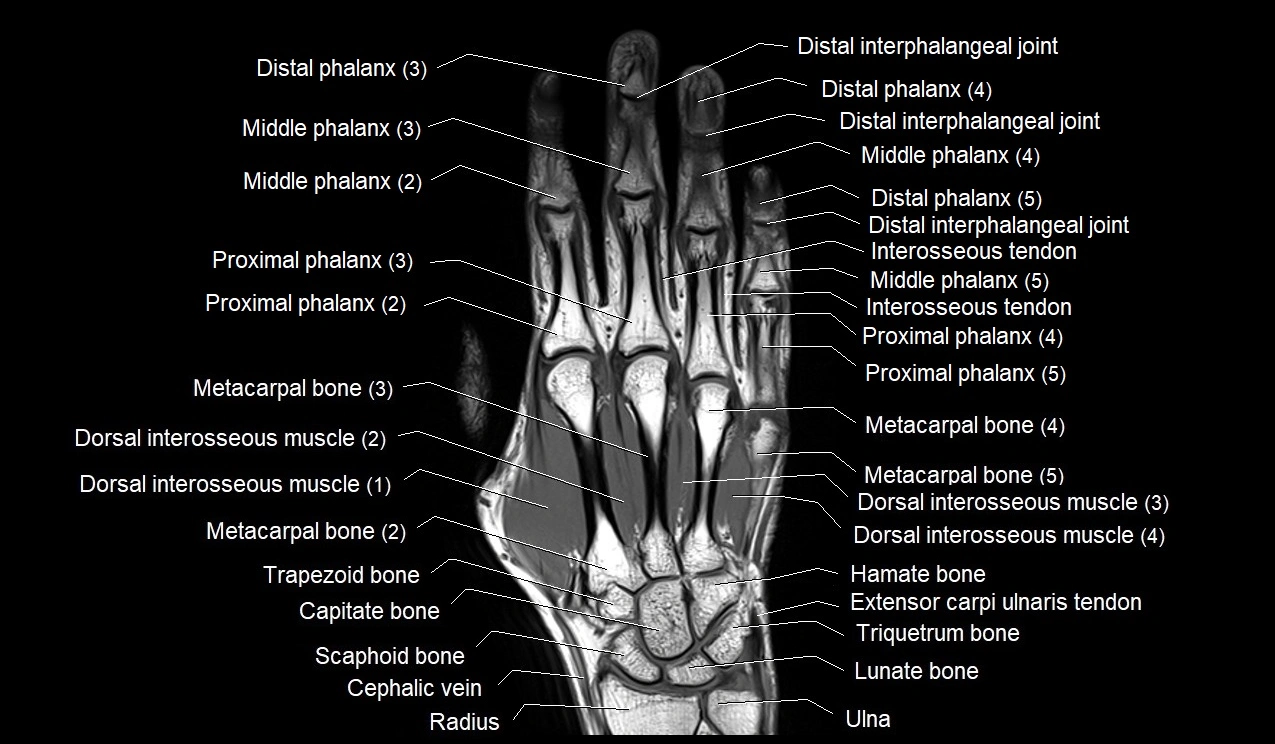

MRI image